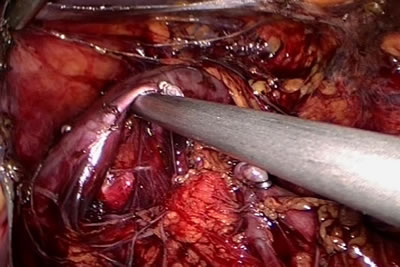

Между наложенными клипсами сосуд рассекается ножницами.

Идет выделение сосудистой ножки почки.

На сосуд накладывается клипса.

Сосуд лигирован клипсой.